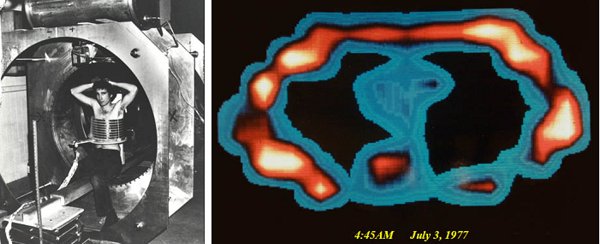

Dr. Damadian in Indomitable for the first attempt at a human MR scan with his chest surrounded by the largest diameter antenna (14" diameter) that Dr. Goldsmith had been able to build at the time that could still successfully generate any MR signal from an interior sample. Also pictured is an adjacent cardiac defibrillator to counter any emergencies that might arise and a cardiologist to administer it if necessary. The scan attempt on Dr. Damadian failed. All that was obtained was a normal EKG. "VISIONARY NONSENSE"

had just turned into a SAD REALITY ! The Goldsmith hypothesis for the failed scan was Dr. Damadian was "too fat" for his coil and was loading the coil's impedance. Larry Minkoff finally gets into Indomitable (weeks later) to test the Goldsmith "too fat" hypothesis. 4:45 AM

July 3, 1977 FIRST EVER MRI IMAGE OF THE LIVE HUMAN BODY !! A cross-section of L. Minkoff's chest at the level of T-8 showing chest walls, lungs, heart, aorta and vertebra, and the suggestion of cardiac chambers within the heart that was initially put down as too good to be true.

"VISIONARY

NONSENSE" The exhilaration of team Indomitable at 4:45 AM July 3, 1977. Hallelujah !